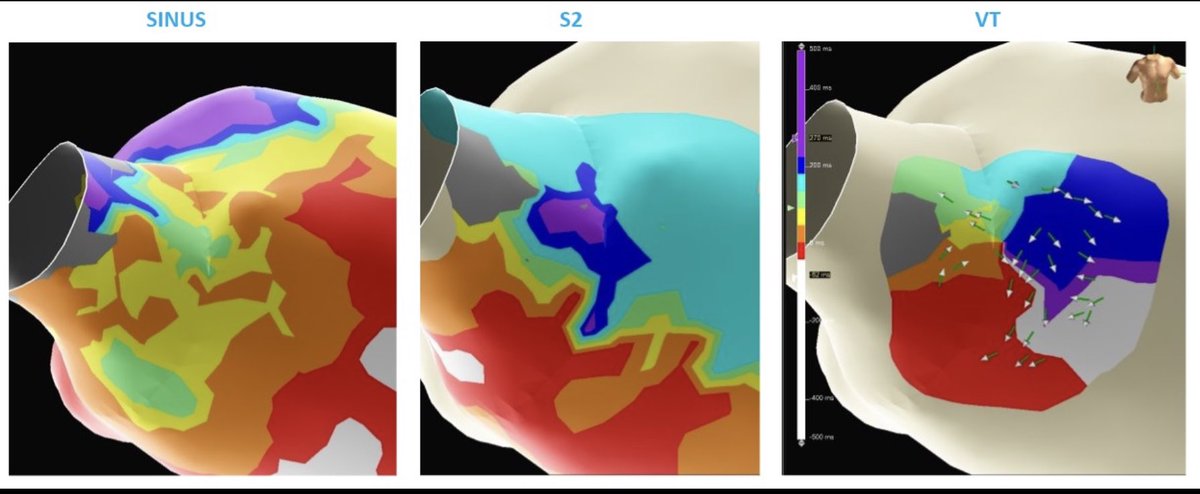

Refining functional LOB with S2 DEEP mapping via NearField, affording us to #StaMP map this Periaortic VT. @Callme_DrNeil @aportasanchez @ivroca @DrRoderickTung @CarinaHardy4 @Dr_Santangeli @omwazni @OCanoPerez @pjsm83 #Epeeps #VT @MonicaKorzon